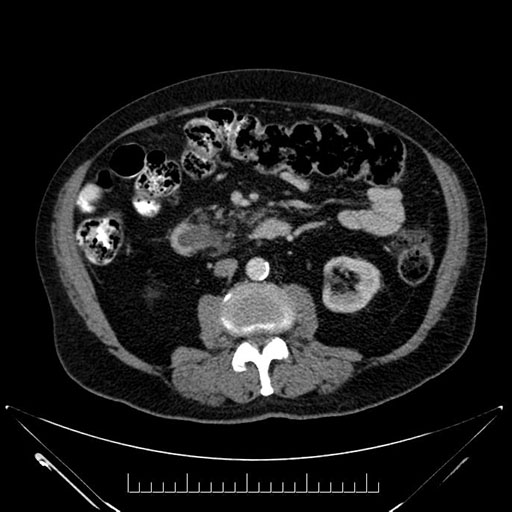

Axial - stented